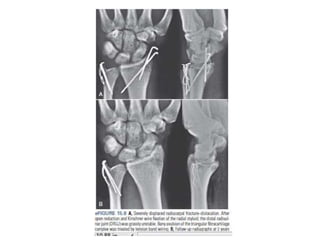

Reducción abierta + Fijación Interna

AO Surgery

Fijación externa combinada con percutanea

Reducción fijación externa combinada con

reducción abierta ,síntesis con agujas de Kirschner

Reducción abierta +Fijación Interna Distal Radius Fractures: Approaches, Indications, and Techniques. Current concept. Ram K. Alluri. 2016 by the American Society for Surgery of the Hand.

Reducción fijación externacombinada con reducción abierta ,síntesis con agujas de Kirschner